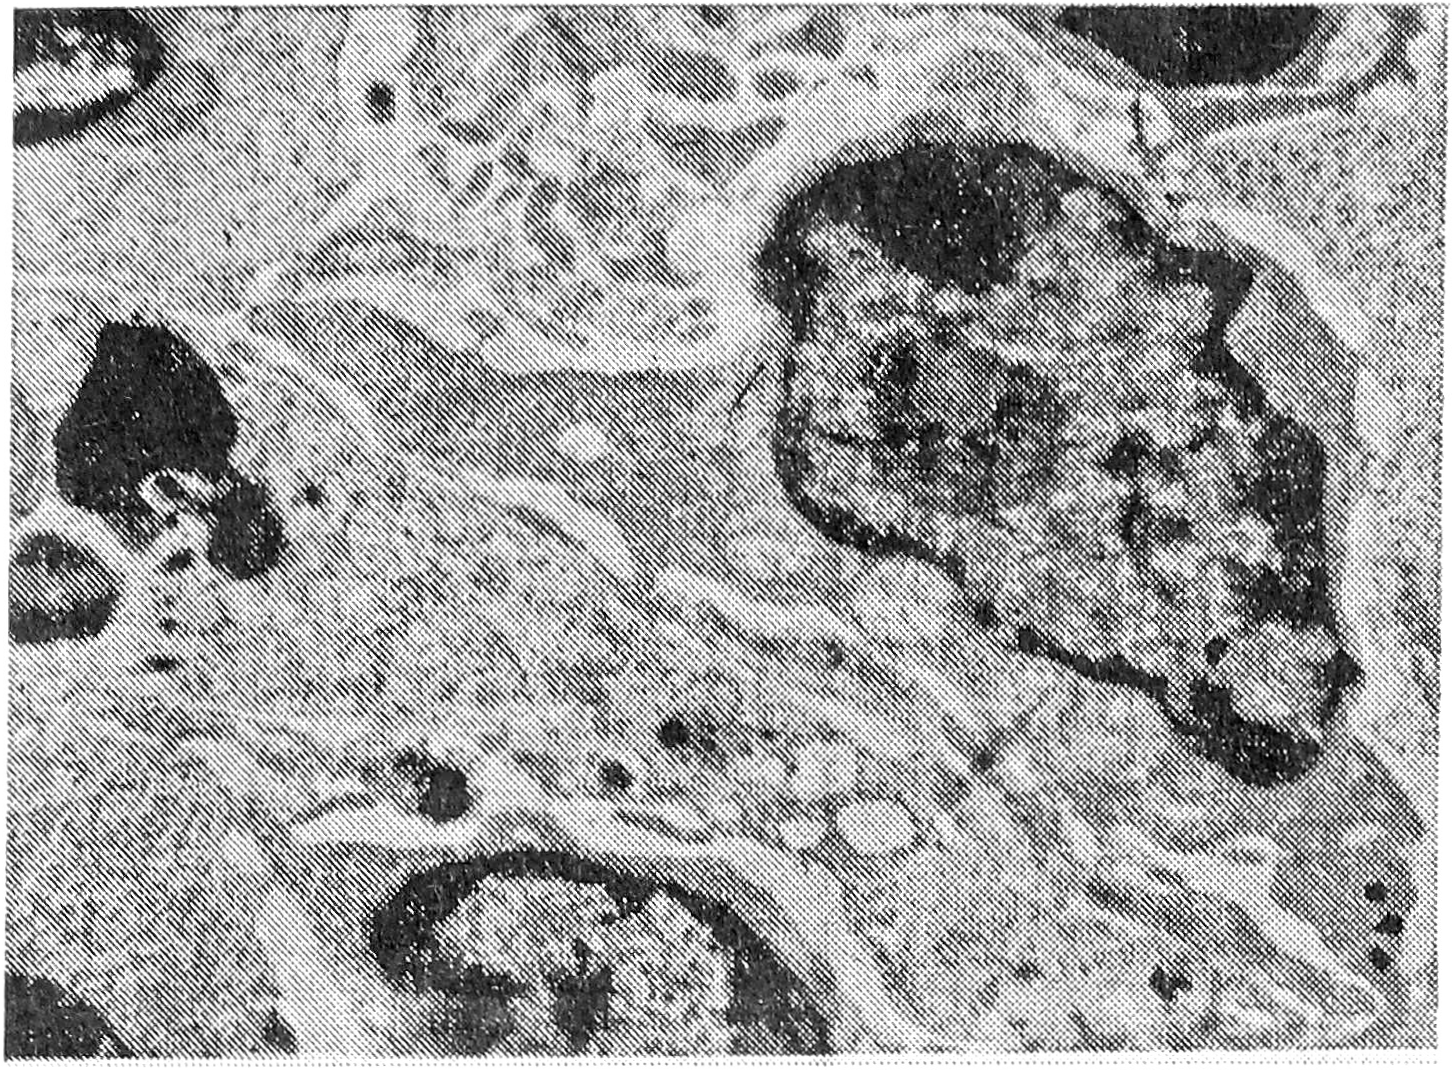

При исследовании под электронным микроскопом было видно, что стенки синусов выстланы литориальными (береговыми) клетками, которые являются продолжением эндотелия лимфатических сосудов. Ультраструктура этих клеток подробно описана [5]. Основные элементы синусов — ретикулярные клетки — имеют размеры от 10 до 25 мкм, овальное ядро с преимущественно диспергированным хроматином и один или два ядрышка. Цитолазма образует выросты и длинные отростки, при помощи которых ретикулярные клетки соединяются друг с другом (десмосомы) и контактируют с лимфоцитами. Из органелл обнаруживаются немногочисленные митохондрии, свободные рибосомы и лизосомы (рис. 1). Ретикулярные клетки являются фиксированными макрофагами [12] и делятся на две функциональные группы — фагоцитирующие и нефагоцитирующие [5], причем в норме, по нашим наблюдениям, преобладают последние. Кроме того, в синусах есть и свободные макрофаги — пришлые клетки моноцитарного происхождения. Их ультраструктура идентична другим интерстициальным макрофагам [12]. Качество таких клеток в норме незначительно. Содержащиеся в синусах лимфоциты представлены в основном так называемыми нетрансформированными формами от 5 до 11 мкм с узким ободком цитоплазмы, единичными и небольшими выростами, округлым ядром без выраженных инвагинаций с преобладанием плотного хроматина и одним ядрышком. Органеллы цитоплазмы незначительны и представлены несколькими митохондриями, свободными рибосомами и единичными лизосомами (рис. 2). Содержание других клеточных элементов в норме в синусах невелико — их характеристика будет приведена ниже при описании опухолевого процесса.

Рис. 2. Нетрансформированный лимфоцит. X 12000.